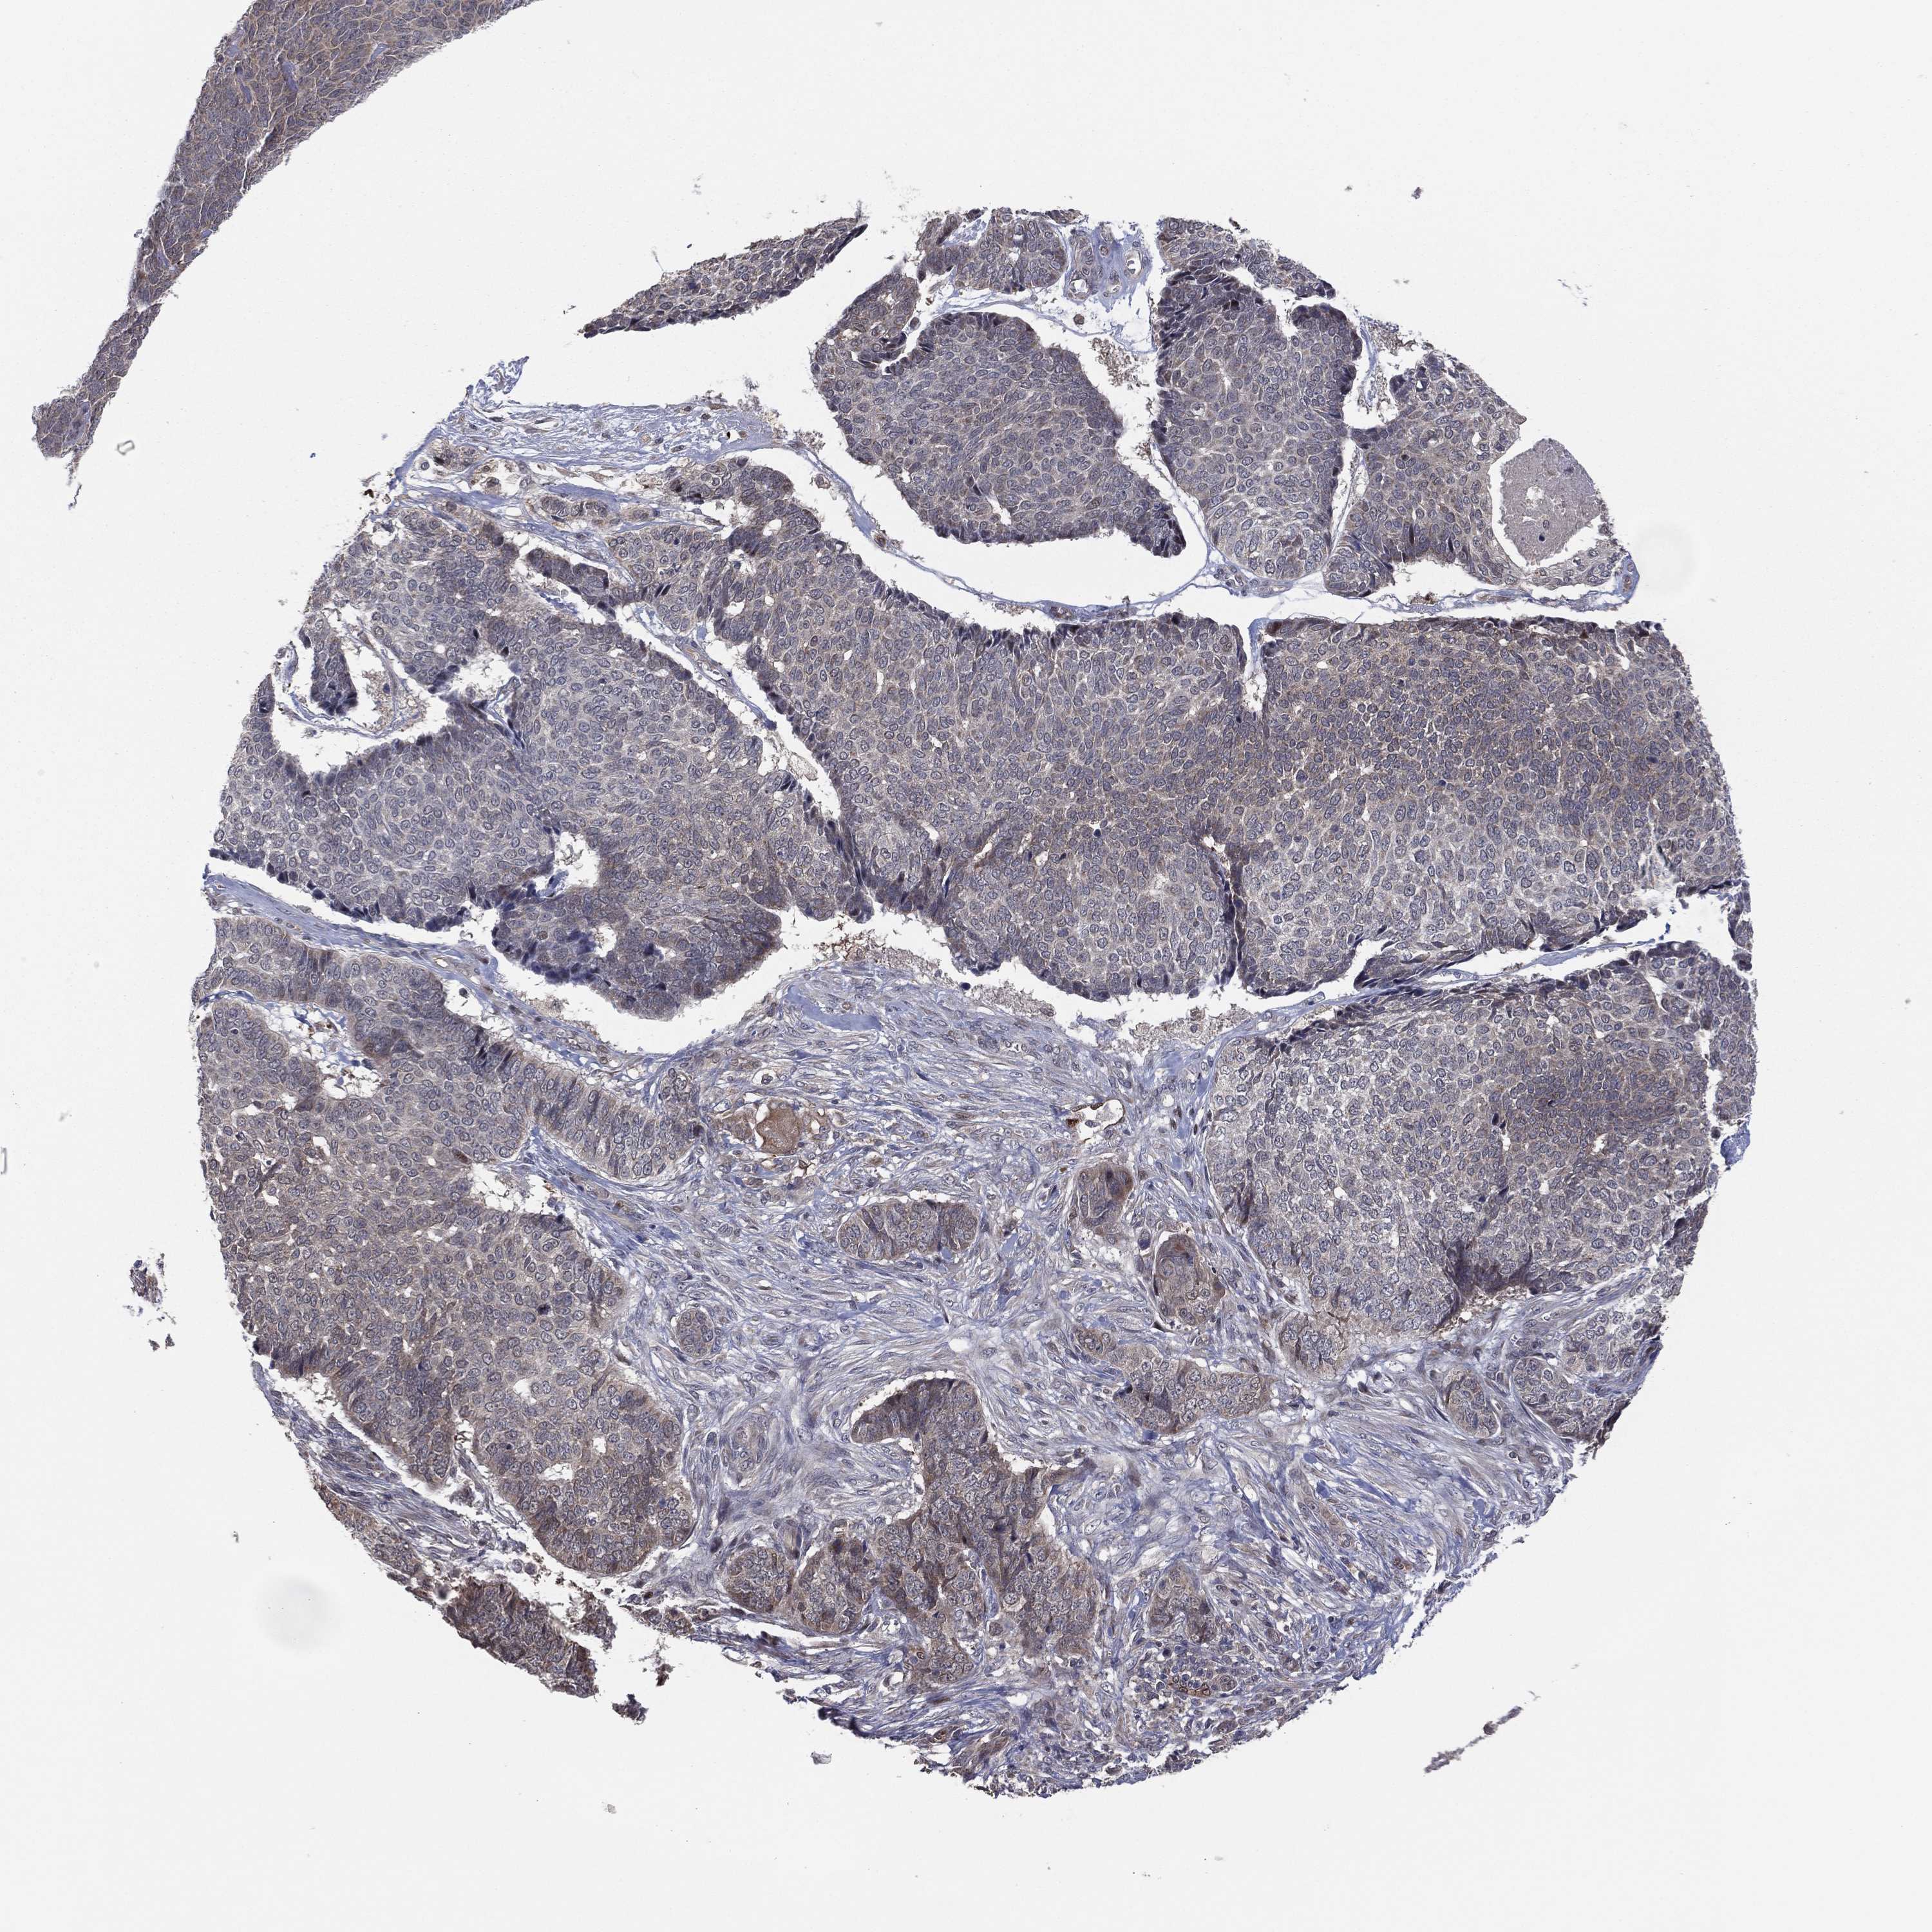

SKIN CANCER - Protein expressioni

A mouse-over function shows sample information and annotation data. Click on an image to view it in a full screen mode. Samples can be filtered based on level of antibody staining by selecting one or several of the following categories: high, medium, low and not detected. The assay and annotation is described here.

Each image is clickable and will lead to virtual microscopy that enables deeper exploration of all samples and also displays staining intensity scores, fraction scores and subcellular localization as well as patient and tissue information for each sample.

Antibody CAB040581

Squamous cell carcinoma, NOS